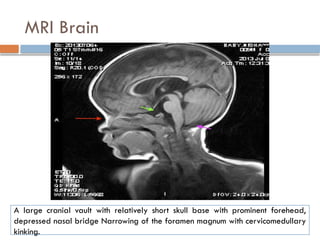

MRI → narrowing of the foramen

magnum and lumbar canal stenosis

MRI Brain

A large cranial vault with relatively short skull base with prominent forehead,

depressed nasal bridge Narrowing of the foramen magnum with cervicomedullary

kinking.

Radiology Examination Head CTScan → neuroanatomic abnormalities consistent with arrested hydrocephalus, enlarged cranial ventricles, changes in the corpus callosum are seen. MRI → narrowing of the foramen magnum and lumbar canal stenosis

MRI Brain A largecranial vault with relatively short skull base with prominent forehead, depressed nasal bridge Narrowing of the foramen magnum with cervicomedullary kinking.